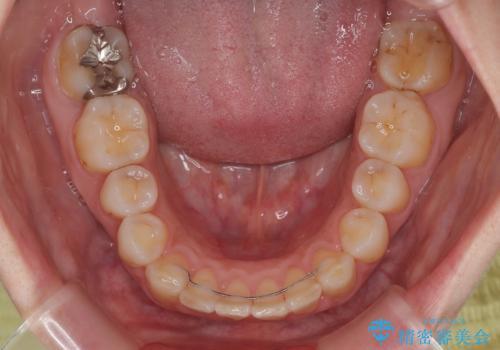

- 矯正装置

- 審美装置

- 1年10ヶ月

骨格的に上顎が前方にあり、上顎のみの抜歯矯正のため、期間はかかることが予想されましたが、スムーズに移動してくれたおかげで、2年弱の短期間で終えることができました。